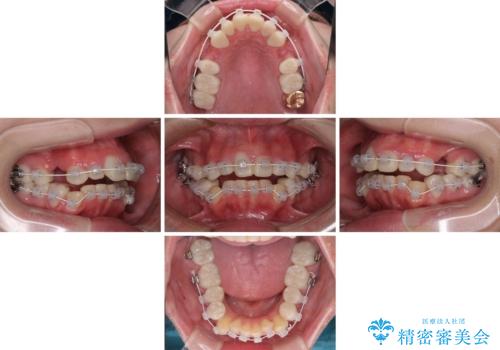

当初はほとんどの歯をむし歯治療のようにオールセラミッククラウンにて補綴治療を行う予定でしたが、仮歯に置き換えた時点で、口元の突出感や下顎前歯の叢生が気になるとのことで、上下左右の第一小臼歯4本を抜歯したワイヤー装置での抜歯矯正を行うこととしました。

矯正治療終了後に、残った歯をオールセラミッククラウンにて補綴治療を行うこととしました。

途中来院が困難な時期があったり、歯周外科処置を行って治癒を待ったりと、治療期間は長くなりましたが、初診時とは比べものにならないくらいきれいに仕上げることができました。